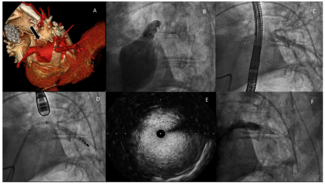

Transfemoral transcatheter aortic valve replacement (TAVR) is quite challenging in patients with tortuous aorta. Recently, the combined method of buddy-wire and long-sheath use was reported.1,2 We experienced 2 cases having tortuous aorta...